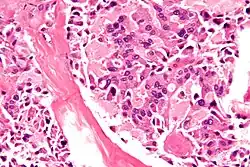

| Micrograph of medullary thyroid carcinoma, as may be seen in MEN 2b. H&E stain. | |